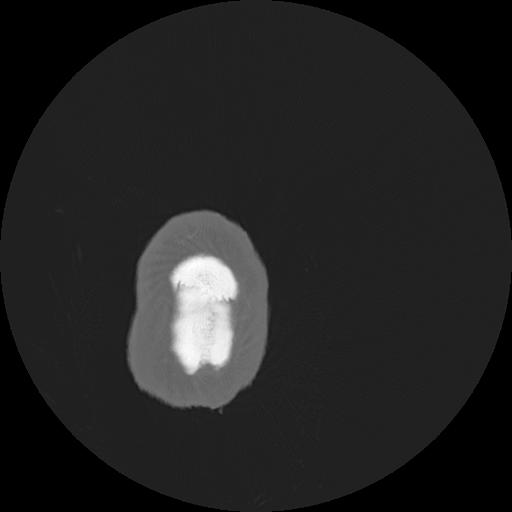

7 HUESO,,Vol,0.5,HUESO,,